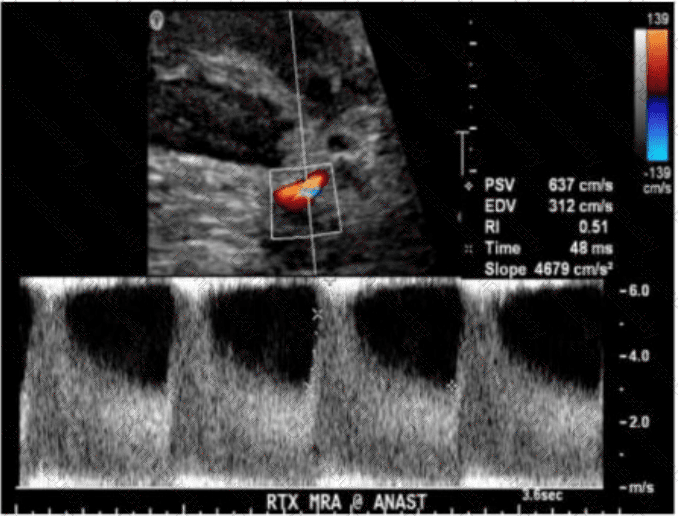

Which condition results in the vascular abnormality shown in this image of a renal transplant?